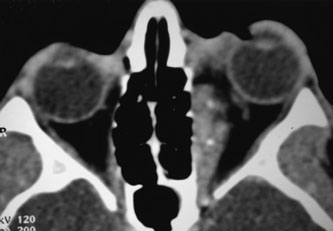

NO FLOW MALFORMATIONS The term no flow malformation (NFM) is appropriate when hemodynamic isolation is demonstrated: that is, the lack of connection of the lesion to the arterial or venous system on imaging studies. These lesions, previously called lymphangiomas, presumably arise embryologically from misdirected vascular anlage tissue capable of differentiating into lymphatics, blood vessels, and other mesodermal elements.88 A spectrum of resulting lesions exists, with hybrid forms composed of combinations of lymphatic and vascular elements.89 Clinical Features No flow malformations are more prevalent in women by a ratio of 1.4 to one.89 Sixty-five percent present in the first decade, and 92% by the end of the third decade.48 However, they may be noted at birth or as late as 73 years of age.89 The channels of an NFM are fully formed at birth, but the lesion can remain inconspicuous until it expands. Lesions may: (a) have purely superficial, multicystic conjunctival (Fig. 9) or eyelid involvement; (b) be localized deep within the orbit; or (c) have both superficial and deep components. Superficial lesions on the eyelid and conjunctiva transilluminate and may appear bluish because of xanthochromic or partially blood-filled cysts.90 Deep lesions can be massive, involving the intraconal, extraconal, preseptal, and postseptal spaces, often resulting in significant cosmetic disfigurement. There are no clinical features of either arterial or venous connection; that is, Valsalva maneuver and alteration of head position do not produce a change in lesion size, and there is no bruit or pulsation.89 Expansion during upper respiratory infections presumably results from lymphoid hyperplasia in response to immune challenge.4,91,92 Bleeding likely results from the rupture of fine blood vessels that course through the flimsy septa of the lymph channels. Clinically, these episodes of expansion manifest as acute proptosis, ptosis, restricted motility, periorbital ecchymosis and swelling, and subconjunctival hemorrhages.3,89 Shrinkage of blood cysts usually occurs over a period of several weeks to several months.89 The probability and timing of future orbital hemorrhage is highly unpredictable. In a study of 30 patients diagnosed with NFM, 40% of patients managed without surgery had additional hemorrhages 2 weeks to 11 years later; 52% of patients who underwent orbitotomy for debulking had additional hemorrhages 4 days to 12 years later.89 Visual loss may result from anisometropic amblyopia, optic nerve compression, or exposure keratopathy from extreme proptosis.89,92 Associated ipsilateral congenital ocular malformations also may be present, including congenital ptosis, congenital strabismus, microcornea, sectorial cataract, heterochromia irides, and abnormal iris vessels.89,90 Associated extraorbital malformations, most commonly the hard and soft palate and paranasal sinuses, were present in 17% of 30 patients studied by Harris and colleagues.89 Very rarely, direct intracranial extension of the NFM can result in cerebral hemorrhage.90 Investigations If NFM is suspected, MRI should be ordered of the orbits and brain to exclude noncontiguous intracranial anomalies.93 Magnetic resonance imaging demonstrates the dilated cystic spaces with either a hypointense (lymphatic cyst) or hyperintense (hemorrhagic cyst) signal on T1-weighted images, and a hyperintense signal on T2-weighted images (Fig. 10, A&B).94Layering may be seen within the cysts if there has been a recent hemorrhage leaving unresorbed blood. The CT scans of patients with a deep NFM show low-density, poorly defined masses behind the orbital septum in the extraconal and intraconal spaces, which may indent the globe.3 Calcification within the mass (Fig. 11) and inhomogeneous enhancement of the rim and focal areas within the lesion may be seen that corresponds to abnormal endothelially lined channels.3 Enlargement of the bony orbit can occur, particularly with combined lesions.3,89 If the diagnosis is still unclear, ultrasonography can be performed. A cystic orbital mass is seen on B-scan. A-scan shows features of a solid, cellular tumor: low reflectivity, regular homogeneous internal structure, and marked sound attenuation through the mass.3,89 Standard pulsed Doppler ultrasound confirms no intrinsic flow within the lesions.